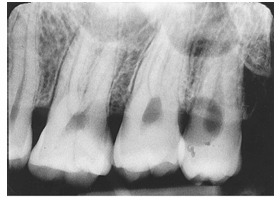

What is the problem with this UNDERDEVELOPED FILM X-ray?

Appears light, Inadequate development time, Developer solution too cool, Inaccurate timer or thermometer, Depleted or contaminated developer solution

How would you resolve this UNDERDEVELOPED FILM X-ray?

Check development time, Check developer temperature, Replace faulty time or thermometer, Replenish developer with fresh solutions as needed